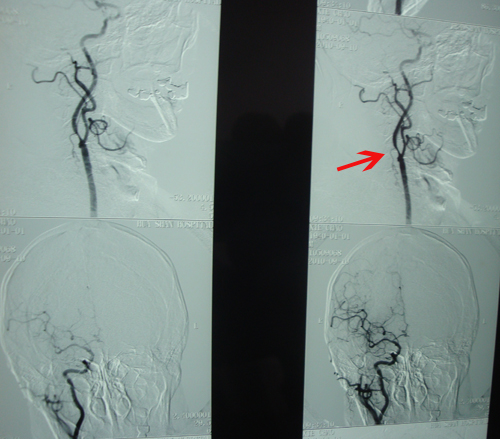

B超示:双颈内动脉狭窄,左侧狭窄70%,右侧80%。

该患者未发作明显中风,于4月前冠脉搭桥术术前检查中B超发现双侧颈动脉狭窄,狭窄程度符合颈动脉内膜剥脱术手术指征。2010年9月16日,协作组张勤奕教授应邀前往上海华山医院,与该院神经外科余波主任共同为患者实施了右侧颈内动脉内膜剥脱术。